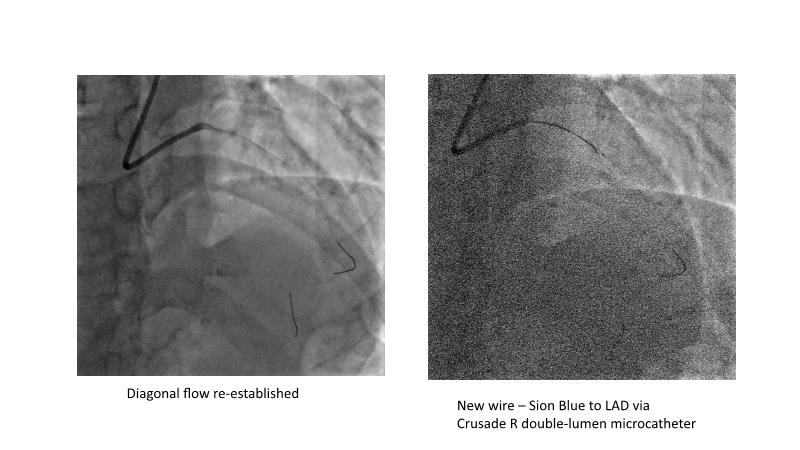

This session is recommended for you if you are seeking insights into the advantages of using IVUS imaging over visual assessment for better outcomes in left main bifurcation procedures. Discuss with experts the benefits of using RotaCUT in lesion preparation for left main bifurcation and explore the impact of high radial strength stents on the procedure's success.

• To see advantages of RotaCUT as part of lesion preparation in left main bifurcation